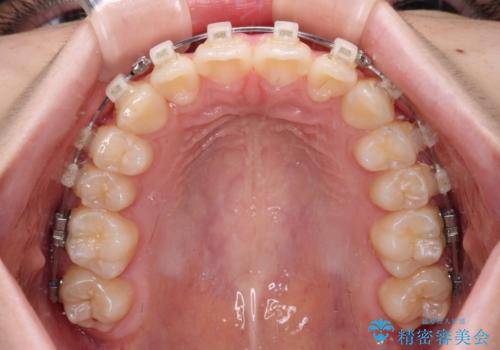

- 矯正装置

- クリアブラケット

- 上下前歯のねじれを気にして来院された患者様です。

ワイヤー矯正でもマウスピース矯正でも対応可能でしたが、マウスピース矯正の自己管理が面倒であること、上顎前歯の捻転が著しいことから、ワイヤー矯正での治療を希望されました。